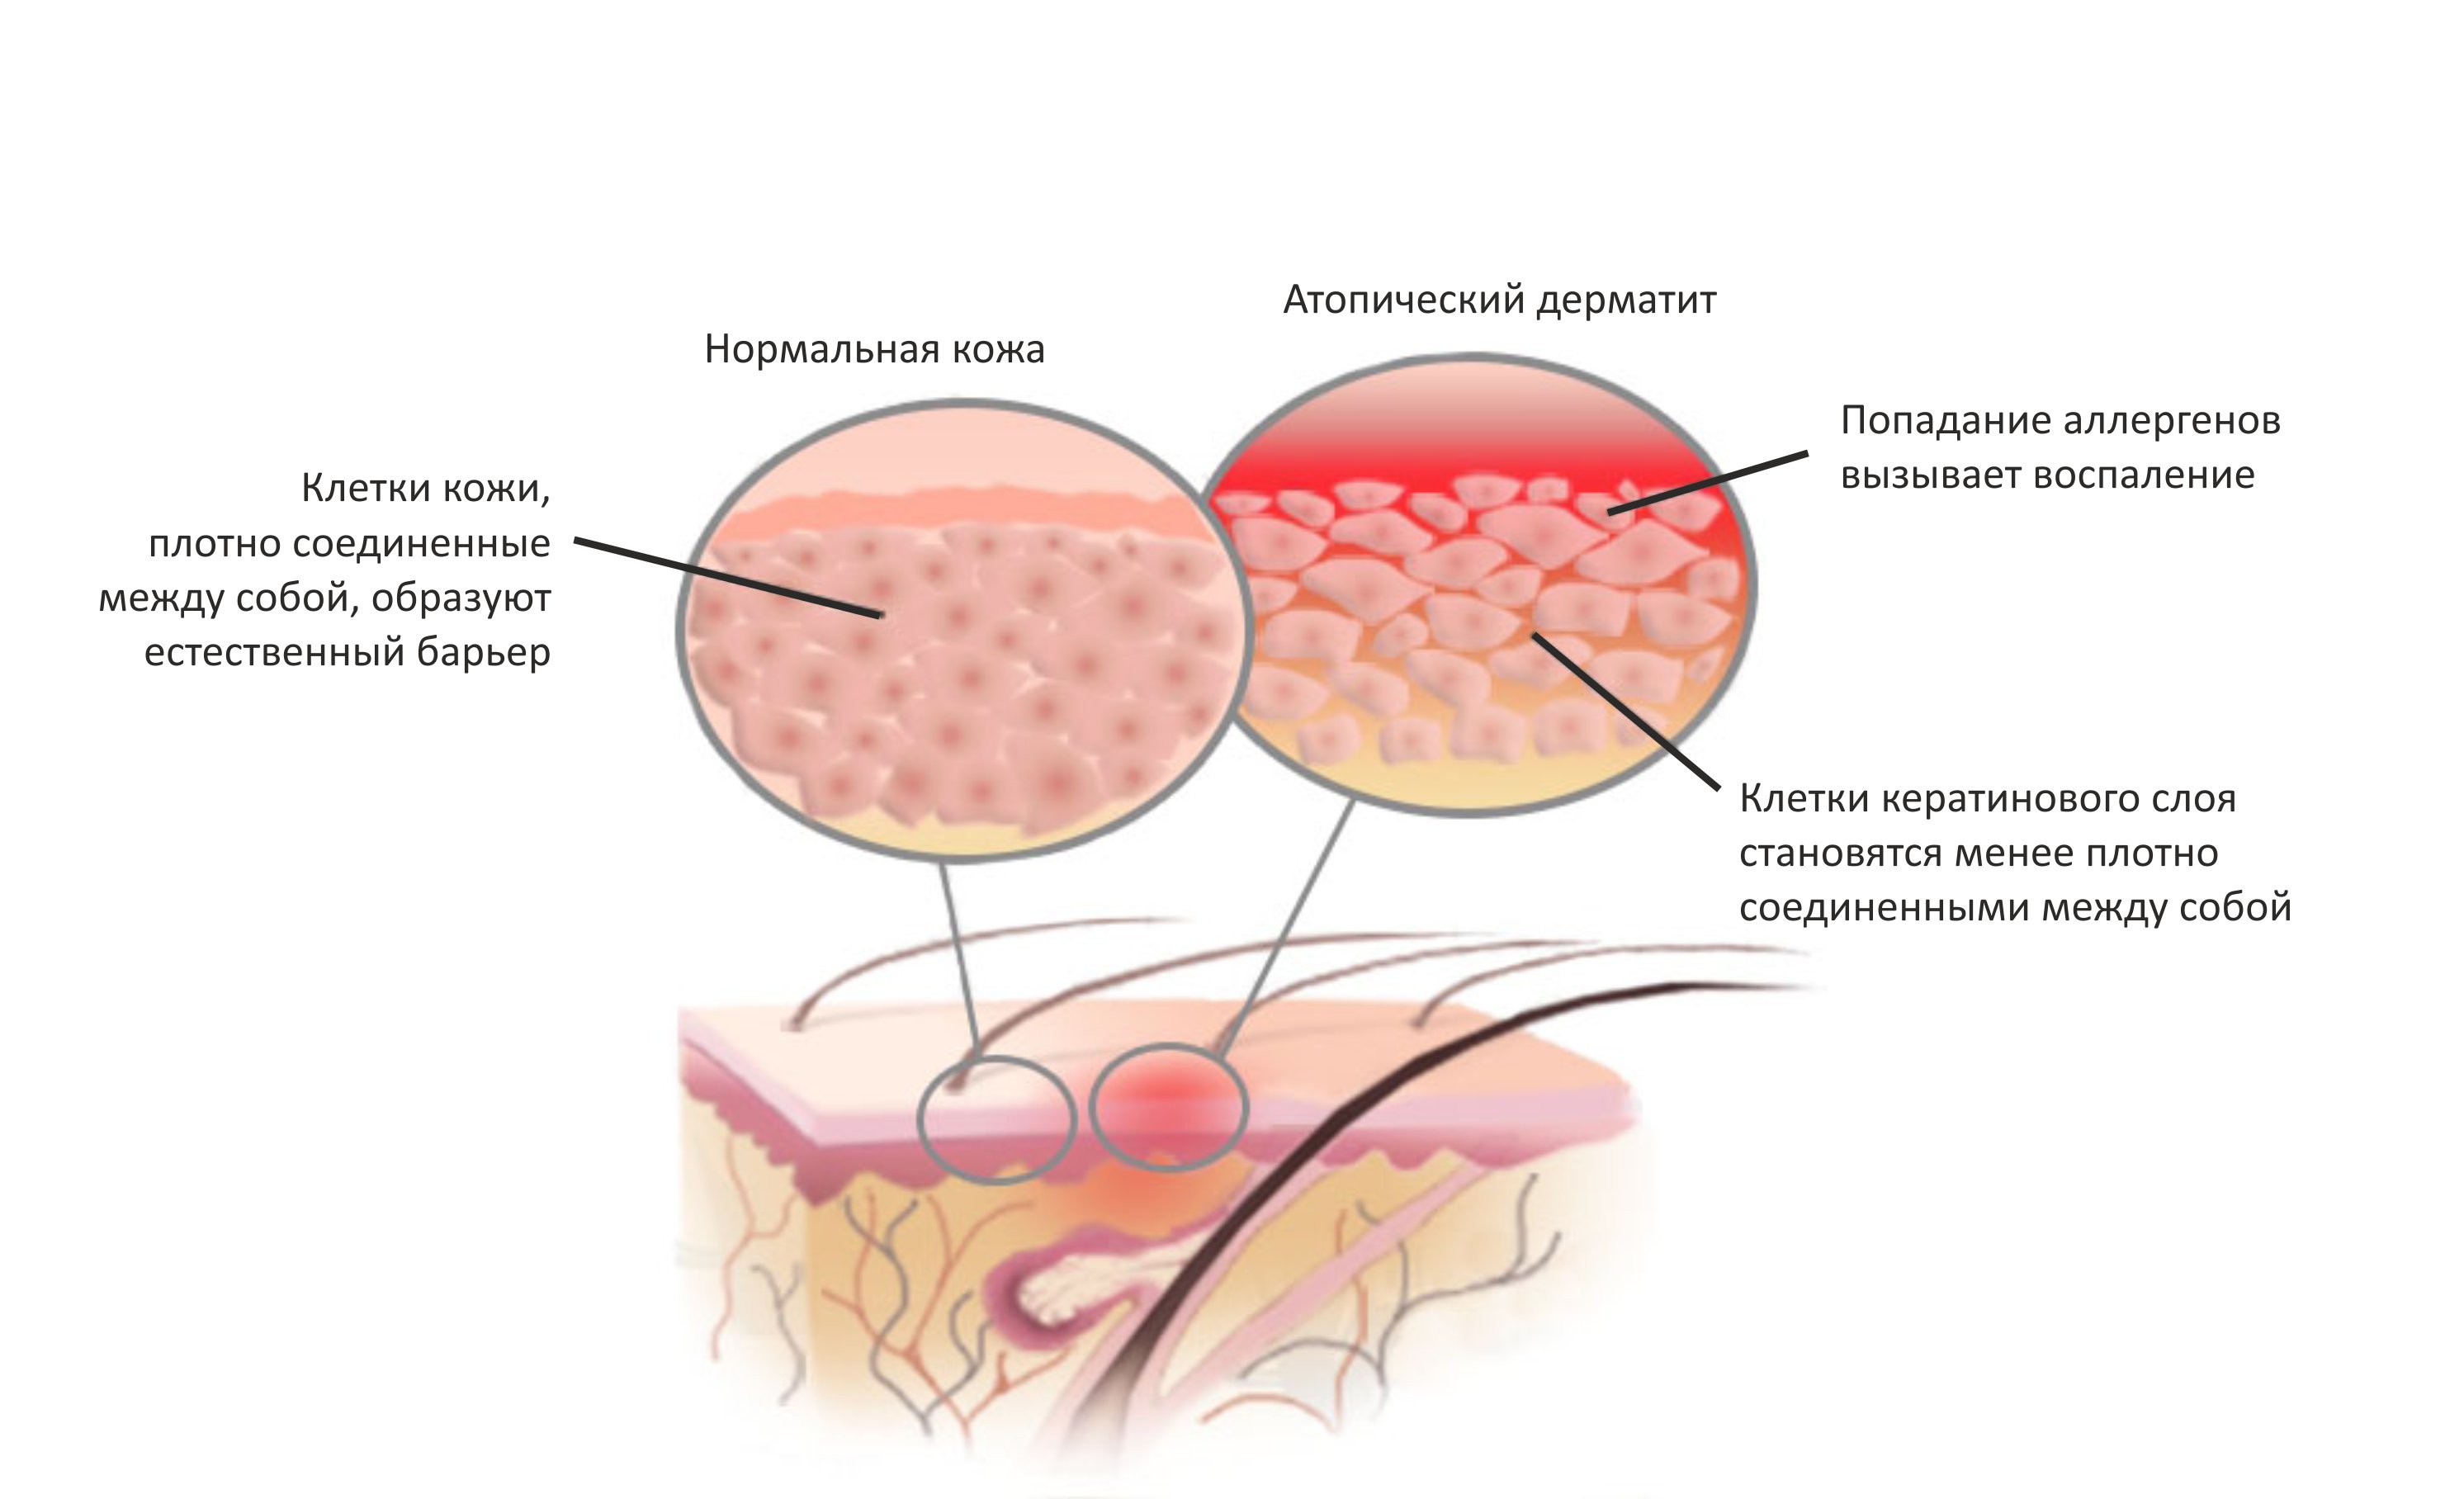

Медицинские снимки и изображения опоясывающего герпес вируса

Раздел: Фотодневник открытий